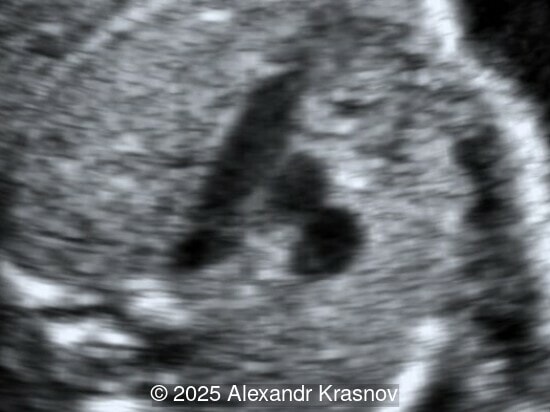

Image 2

Our ultrasound showed biometry data corresponding to 21 weeks of gestation. During echocardiography, an abnormal drainage of the pulmonary veins was detected in which the pulmonary veins drain into a venous collector linked to the superior vena cava. The four-chamber view and the three-vessel view were altered and raised suspicion of a pathology. The grayscale and color Doppler images of the four-chamber view indicate a smooth posterior wall of the left atrium, increased distance between the left atrium and the descending aorta and the absence of pulmonary veins entering the left atrium (Image 1, 2; Video 1, 2). In the three-vessel view, the diameter of the superior vena cava appears larger than that of the aorta (Image 3, Video 3). In the images of the venae cava, a significant difference is seen between the diameters of the inferior and superior vena cava with significant enlargement of the superior vena cava (Image 4, Video 4). Additionally, there is a pulmonary venous confluent chamber (“twig sign”) behind the left atrium (Image and Video 5). A vertical ascending vein connects the confluent chamber with the superior vena cava where it drains blood from the pulmonary veins (Images 6, 7; Video 6).

Direct markers are based on anatomical features in TAPVR, and their presence usually confirms the diagnosis. Some appear in all types of TAPVR, and others are specific to particular types. A lack of connection between the pulmonary veins and the left atrium or the presence of a confluent chamber can be found in all types of TAPVR. Whereas the presence of an ascending or descending vertical vein is found in supracardiac or infracardiac types. Normal entry of a left and right pulmonary vein at the posterior wall of the left atrium (horn‑like insertion) is absent, which leads to a completely smooth posterior wall in the four-chamber view [6,7]. The “twig sign” represents the entry of the pulmonary veins into a confluent chamber behind the left atrium [7], and is visible in the four‑chamber view except in the cardiac type. In the cardiac type, the confluent vein is located more inferiorly, below the plane of the four‑chamber view and does not form a twig sign, making it more difficult to detect [5]. In supracardiac TAPVR, an ascending vertical vein can be observed in the 3-vessel tracheal view as an additional vessel, usually located at the left of the main pulmonary artery. In infracardiac TAPVR, the descending vertical vein can be seen as an additional vein in the axial abdominal plane [8].